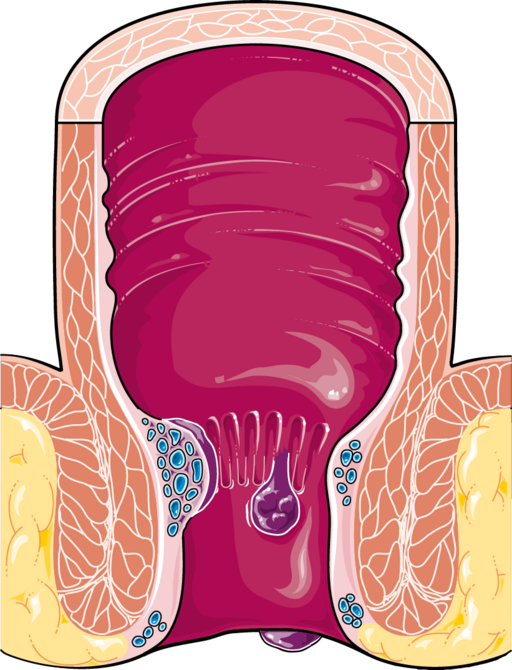

Hämorrhoiden

DefinitionHämorrhoiden

Hämorrhoiden sind eine Vergrößerung des arteriovenösen Geflechts im Rektum (Corpus cavernosum recti) mit Ausbildung eines Hämorrhoidalpolsters.

Klinisch fallen sie häufig durch hellrote Blutungen, Juckreiz und Brennen auf.

Digestive system - Hemorrhoids -- Smart-Servier.png von Laboratoires Servier, CC BY-SA 3.0, via Wikimedia Commons